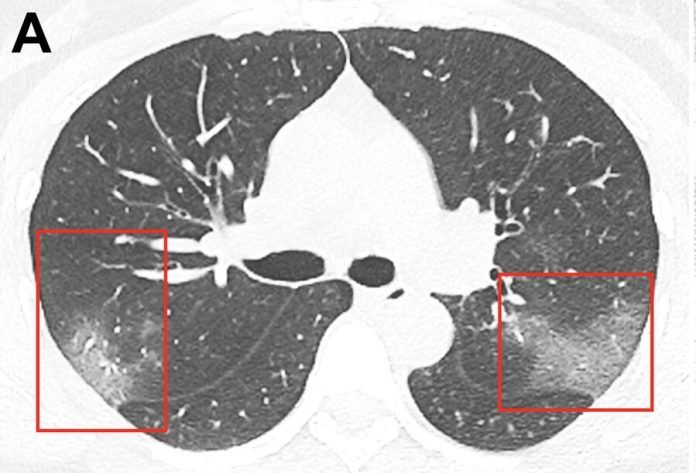

it is Noted that the image was obtained using computer tomography 33-year-old resident of Lanzhou city. Previously, she was hospitalized with a temperature of 39 degrees.

So, in a single shot recorded opacities that create a dulling effect. In the picture, taken three days later, it is noticeable that the affected area becomes larger.

“On the basis of epidemiological characteristics, clinical manifestations, imaging of the thorax and laboratory data was diagnosed with “pneumonia 2019-nСоV”, – said the medics.